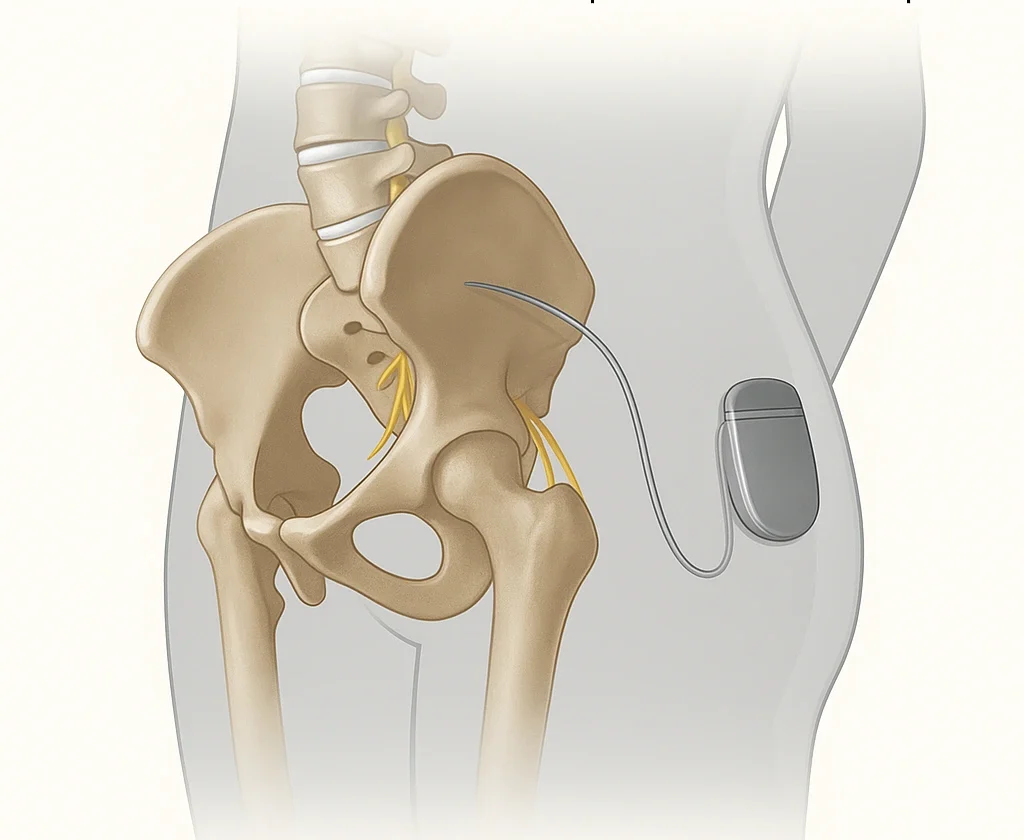

Neuromodulation of sacral roots

Sacral root neuromodulation is an innovative technique used to treat certain urinary or pelvic disorders that are resistant to conventional treatments. It regulates the nerve activity responsible for controlling the bladder, rectum and perineum.

The goal of neuromodulation is to “retrain” the nervous system by gently stimulating the sacral nerve roots (primarily S3) with low-frequency electrical impulses. This technique allows for: • reduce overactive bladder, • restore a normal sensation of urinary urge • improve or trigger bladder emptying, • relieve chronic pelvic pain.Treatment sequence

Step 1: Testing phase (or evaluation phase) • Performed on an outpatient basis, under local or light anesthesia. • Implantation of a thin electrode near the sacral root (often S3). • Connection to an external neurostimulator for 1 to 3 weeks. • Objective: to evaluate the effectiveness on urinary and pelvic symptoms. • The patient keeps a voiding diary to note improvements. If the test phase shows an improvement ≥ 50%, the final implantation is carried out. Step 2: Neurostimulator Implantation • Performed under light general anesthesia. • The stimulator (the size of a USB key) is implanted under the skin, at the top of the buttock. • Permanent connection to the test phase electrode. • Programmable and adjustable device available for consultation.Post-operative follow-up

Let me introduce you to the principle of sacral neuromodulation. It is a minimally invasive treatment that gently stimulates the sacral nerves to improve urinary control and relieve chronic pelvic disorders .